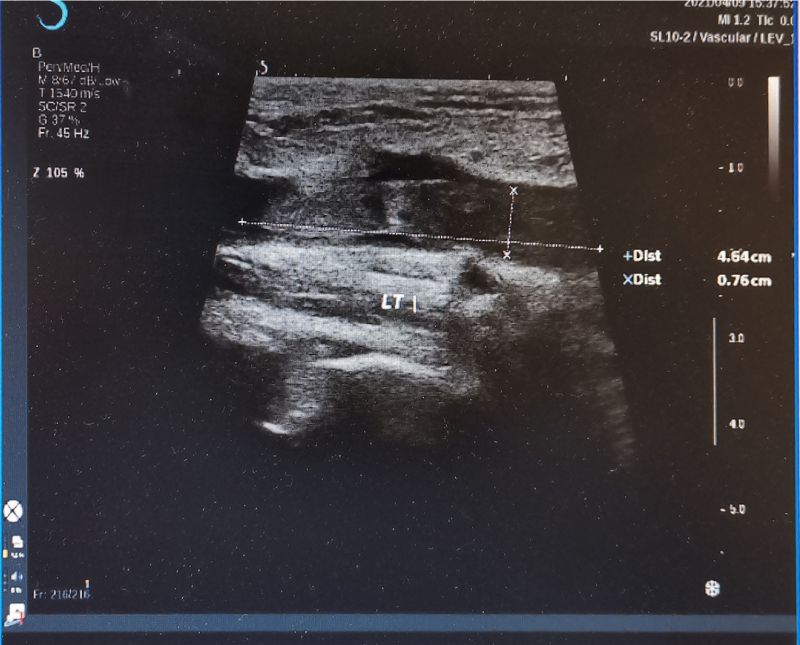

此后,张先生接受了下肢静脉超声、CT肺动脉造影检查。检查发现,他的双肺多发肺栓塞,左侧股总静脉中存有游离血栓。对此,东院全科医学科立即嘱张先生左下肢制动,请血管外科医师急会诊。据介绍,张先生的症状非常不典型,但是危险程度极高,一旦左下肢静脉的游离血栓再次脱落,将危及生命。此后,他及时转入东院血管外科,第一时间接受了手术治疗。术后再无头晕症状,也没有不经意间跌倒的情况发生,并于近日出院。